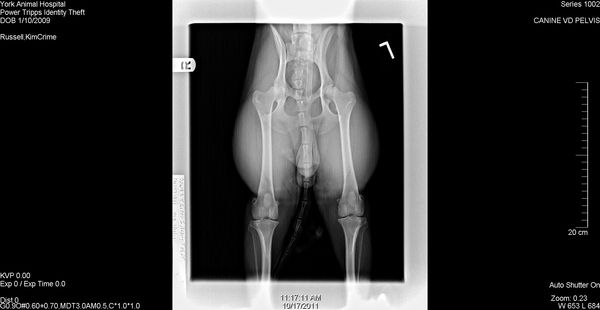

CEA DNA Normal, CERF Normal, OFA Excellent, TNS Normal

2009/1/10AKC DN23731101 CEA DNA Normal by parentage, CERF Normal, OFA Excellent, TNS Normal